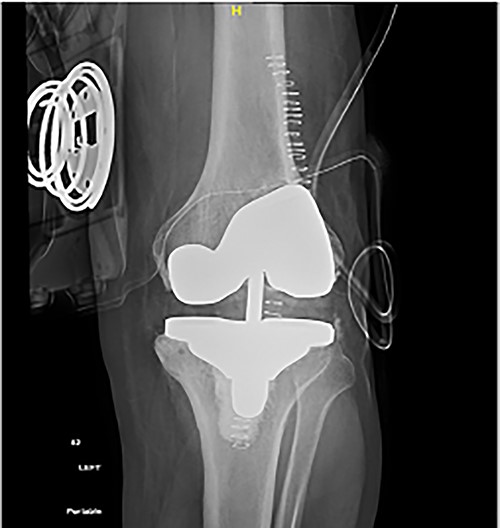

At the 2-year follow-up visit, the patient’s active ROM continued to be between 4 and 85° (Fig. 7). Patient’s functional outcome score was measured using the Knee Injury and Osteoarthritis Outcome Score pre- and post-operatively, with marked improvement in scores noted from 45 to 76%.

Post-operative plain radiographs at 2-year follow-up visit; (A) 2-year post-operative AP radiograph showing implant in place with decreased lateral gap sized to be 1.57; (B) 2-year post-operative lateral radiograph of the knee showing implant in a satisfactory position.